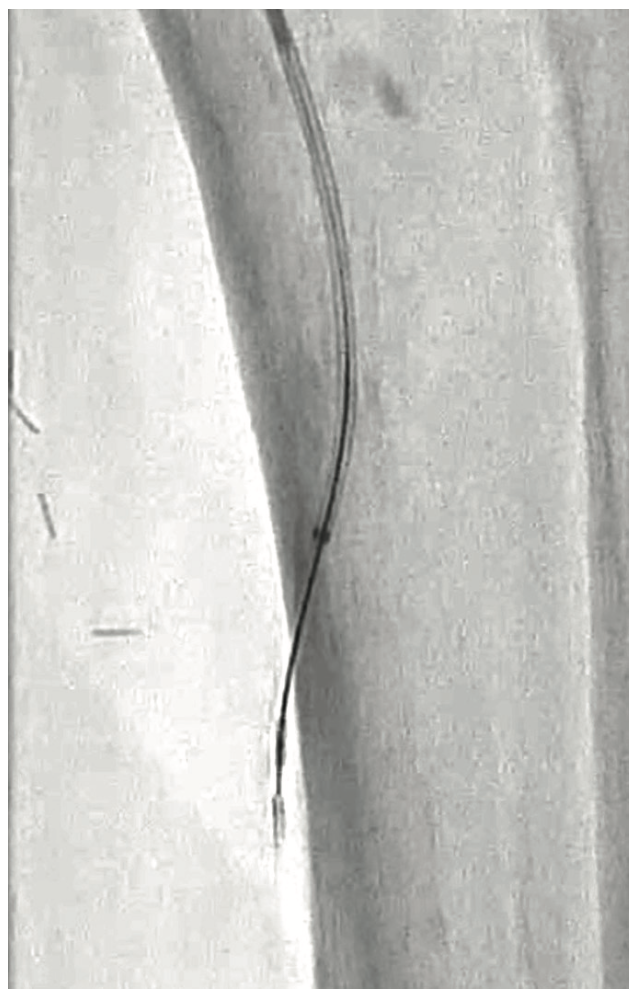

In cases where the tibial vessels do not reconstitute above the ankle, we choose to perform a modified Schmidt access of the occluded vessel. This is a technique where the operator accesses the occluded portion of the vessel using ultrasound guidance. Access into the distal occluded PT was performed using a V-18 wire. An antegrade access with a 5 French sheath was utilized to advance an .035-inch Navicross catheter (Terumo) to engage the proximally occluded PT using an Astato .014-inch 20-gram tip wire (Figure 3). Using the tunneling technique, we were able to advance the retrograde V-18 wire into the antegrade Navicross catheter (Figure 4). We chose to floss a Viper wire between the antegrade sheath and the pedal access. After plaque modification in the PT followed by balloon angioplasty, an .014-inch catheter was advanced inside the Navicross over the flossed Viper wire (from the CFA to the PT access point). At this stage, the Viper wire was removed and a Regalia .014-inch wire was advanced into the plantar circulation (Figure 5).